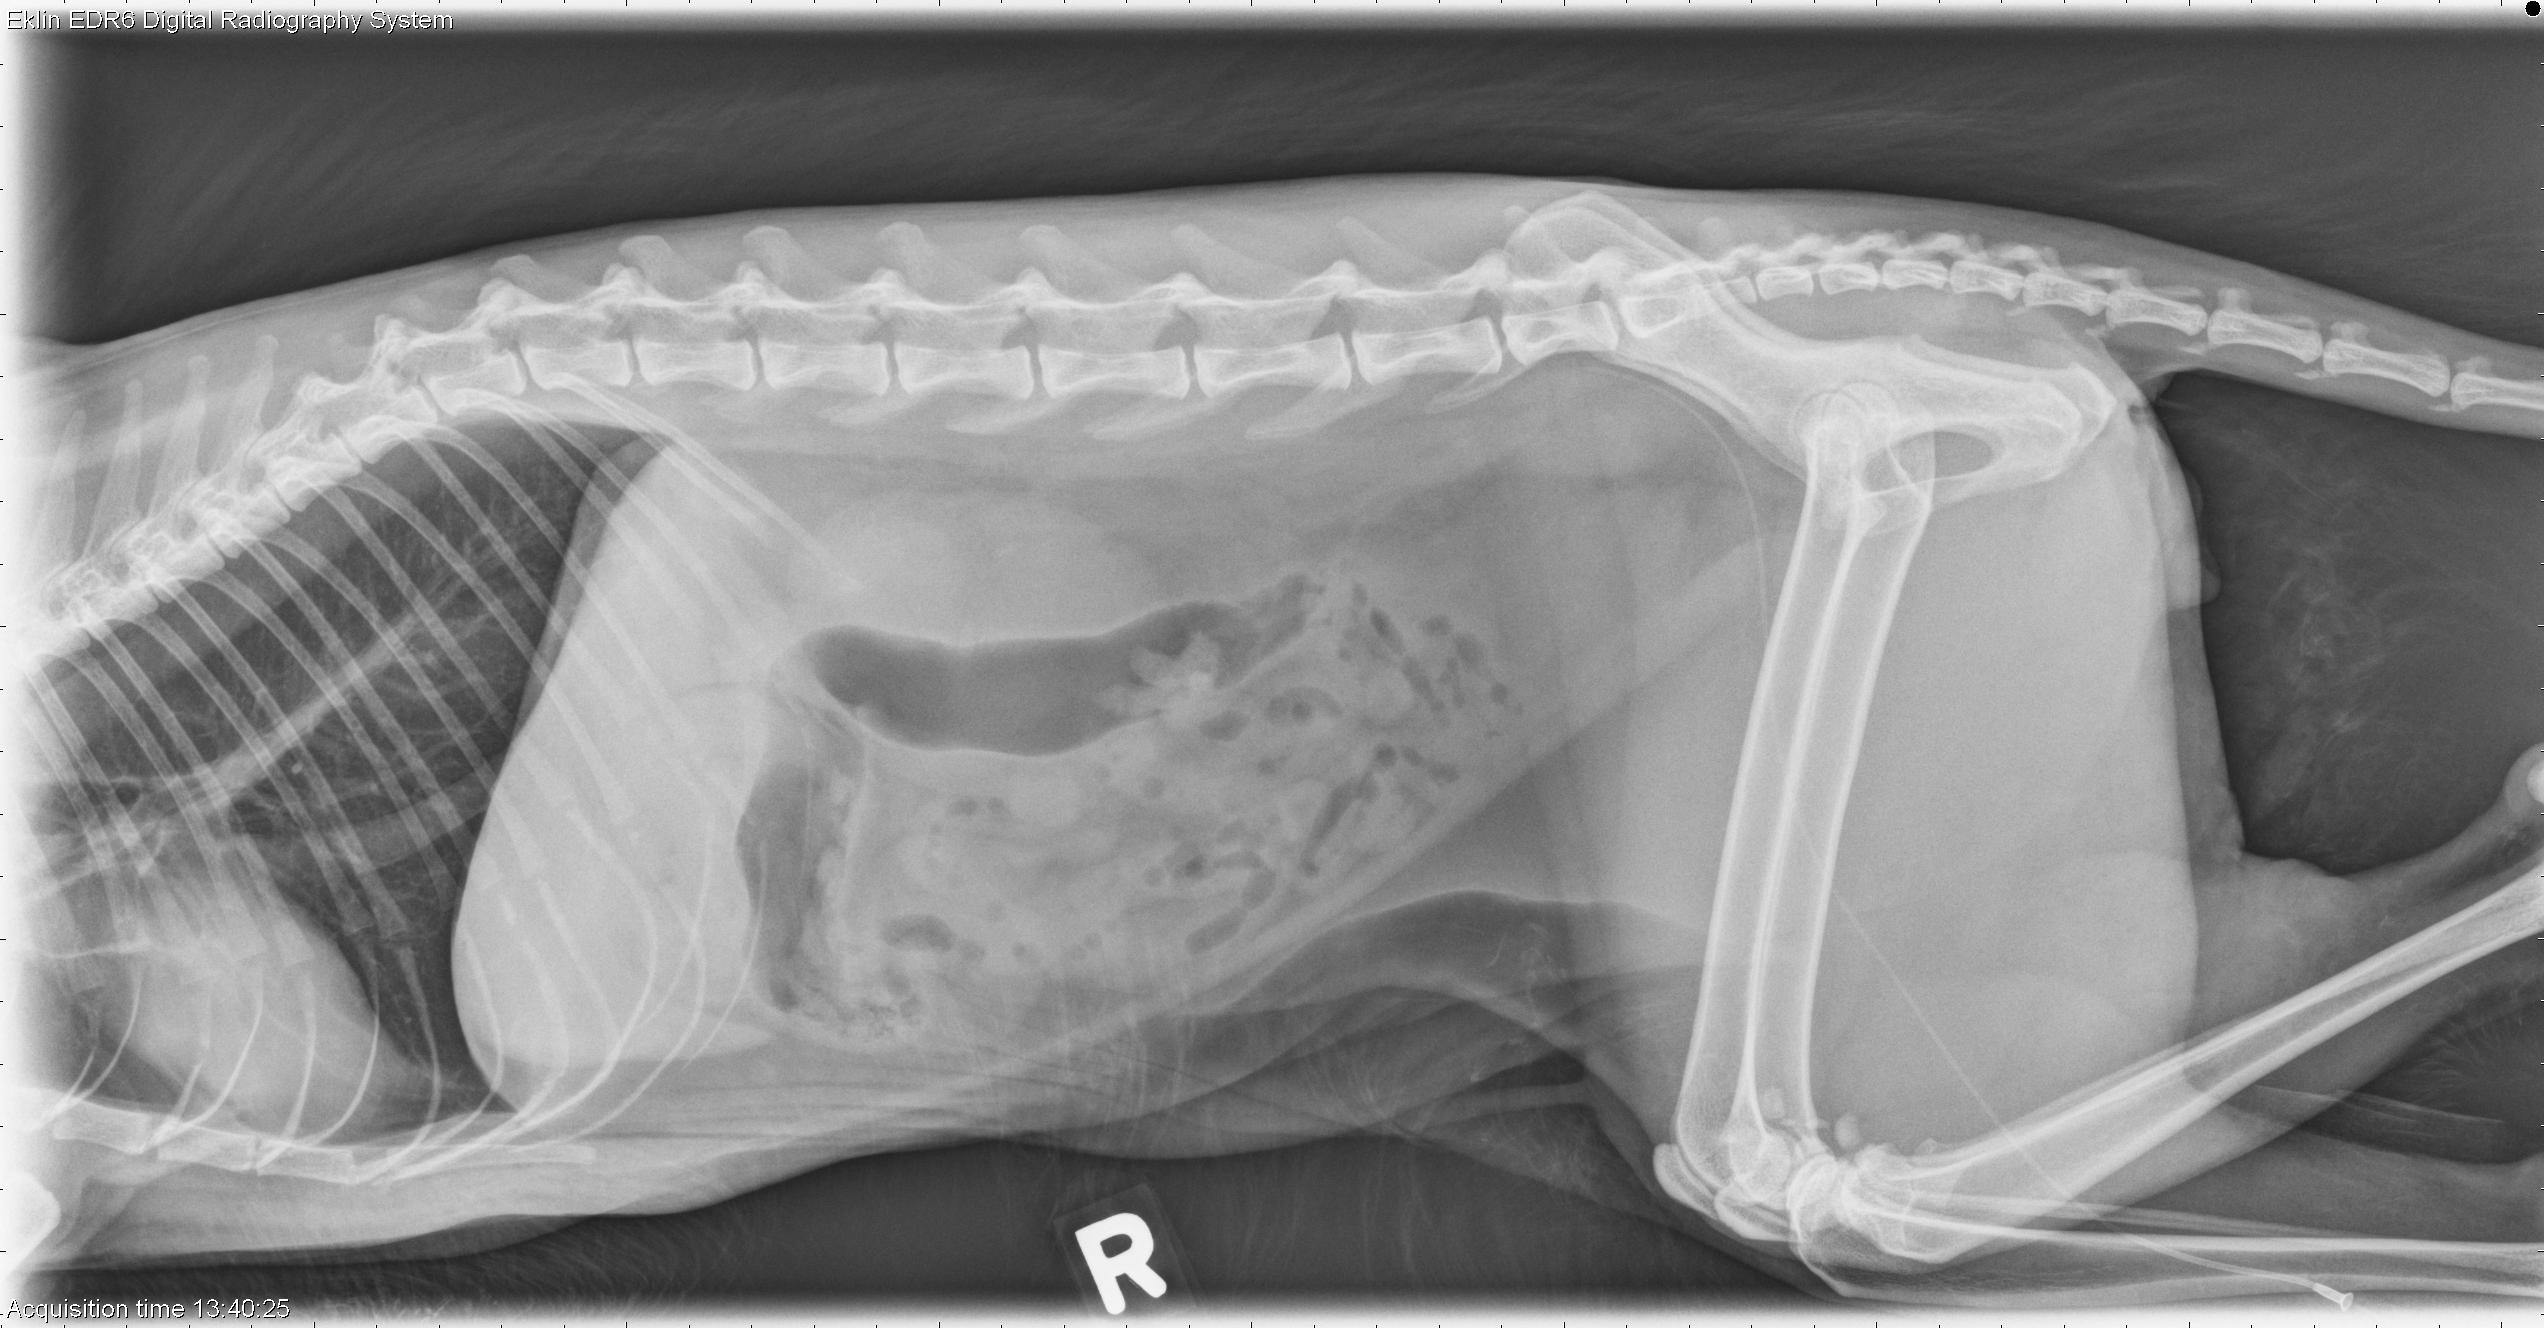

This week’s case is a 9-year-old male neutered Domestic Shorthair cat with chronic renal failure. What are your findings?

R LAT Abdomen

The liver and gastrointestinal tract appear normal. The left kidney is small with an irregular border and central calculi in the pelvis. The right kidney is enlarged and has a flattened cranial pole on the ventrodorsal projection. Calculi are present in the renal pelvis.

• Bilateral chronic renal change

• Right renal enlargement may be due to compensatory hypertrophy or hydronephrosis (ureteral obstruction).

• Right renal hydronephrosis secondary to right ureteral obstruction (mucus plug) and moderate hypertrophy (histopathology)

Ultrasound imaging showed an enlarged right kidney with marked pelvic dilation and poorly defined architecture.